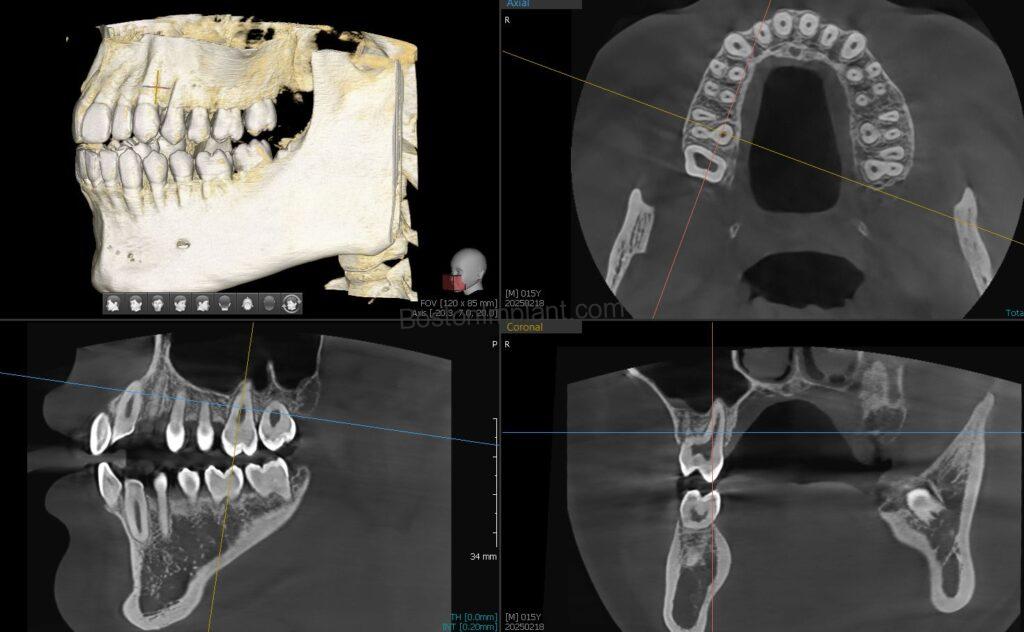

When I was a kid, I enjoyed making animations by flipping pages. Each picture was a static image, but when combined, they created an animation.

Similarly, with CBCT, multiple 2-dimensional images are combined to create a 3-dimensional image. This allows us to see details that are not visible with conventional X-rays.

1. Planning Dental Implants: By analyzing bone shape in a three-dimensional view, we can find the optimal position and angle for dental implants. After planning, we create a surgical guide to accurately transfer the plan to the actual surgery. (Please check out our information on dental implant surgical guides!)

6. Orthodontics (Invisalign, Clear Aligners, Teeth Straightening): This is a newer application for CBCT in dentistry, but Invisalign and clear aligner patients can greatly benefit. In orthodontics, teeth (specifically their roots) move within the bone. Traditionally, we estimated root shapes based on the visible crown. Now, with 3D root and bone images from CBCT, we eliminate guesswork. This allows for more accurate simulation of root movements, ensuring the best possible outcome for your teeth straightening journey.